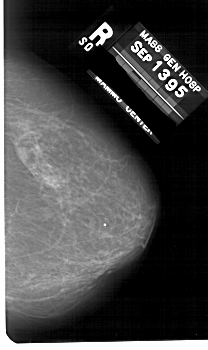

A_1676_1.RIGHT_CC

RIGHT_CC LINES 5236 PIXELS_PER_LINE 3106 BITS_PER_PIXEL 12 RESOLUTION 43.5 NON_OVERLAY

RIGHT_MLO LINES 5491 PIXELS_PER_LINE 3436 BITS_PER_PIXEL 12 RESOLUTION 43.5 NON_OVERLAY